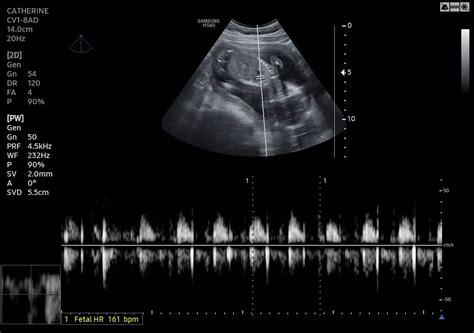

During the scan, you’ll lie on an examination table. A sonographer (a specially trained technician) will apply a clear gel to your abdomen. This gel helps the ultrasound waves travel easily. They’ll then move a handheld device called a transducer over your belly. The transducer sends out sound waves, which bounce off the baby and the mother’s organs, creating images on a screen. The sonographer will carefully examine these images, measuring different parts of the baby and assessing the mother’s health. The images can also be saved and used for future reference, in case a comparison is needed.

During the scan, you might see your baby’s movements and even hear their heartbeat. The sonographer will usually explain what they’re looking at and answer any questions you have. Sometimes, they might ask you to change positions to get a better view. After the scan, you’ll be able to get back to your regular routine. The sonographer will typically give you a preliminary report, and the doctor will review the images in detail and discuss the results with you. Keep in mind that sometimes, additional tests are needed, depending on what the ultrasound reveals. Don’t hesitate to ask questions; it’s your pregnancy, and you deserve to understand what’s happening.